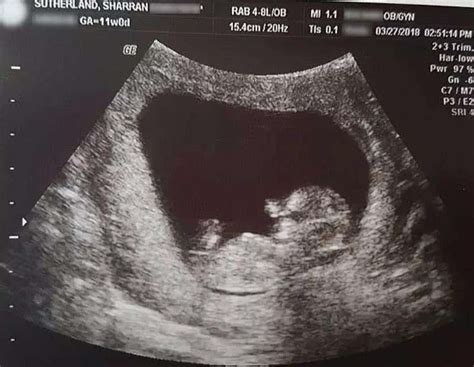

妊娠期母体七情”的调节与子女才干的发展有很大的关系。研究表明,胎教是教育的启蒙。胎宝宝在子宫内通过胎盘接受母体供给的营养和母体神经反射传递的信息,其脑细胞在分化、成熟的过程中不断地接受母亲的调节与训练。

我们不得不承认,胎宝宝是有感知的生命,宝宝聪明才干的启蒙教育是在胎儿期进行的。对胎宝宝进行及时合理的胎教训练以便使胎宝宝更好地发育,是当代新家庭应该高度重视的课题。